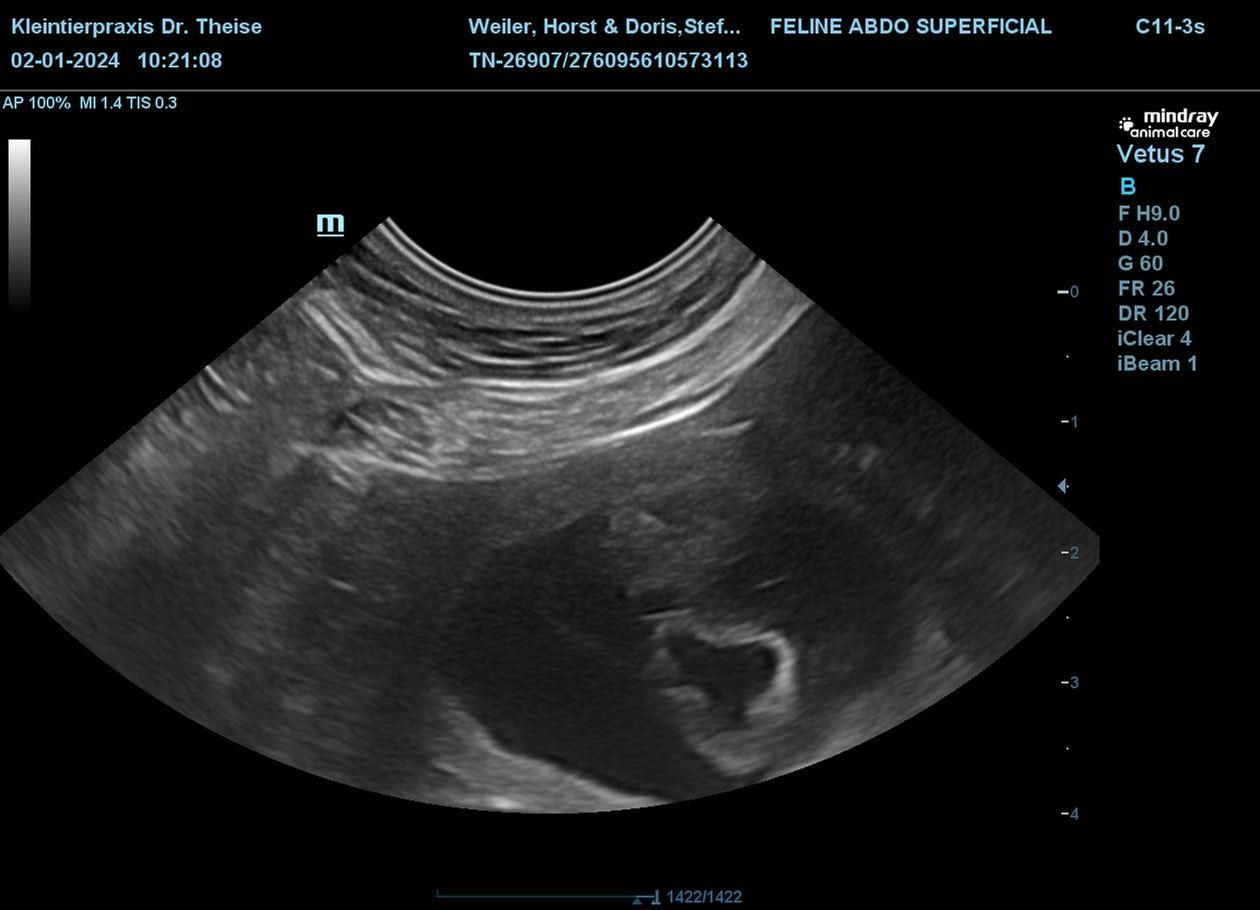

Nachdem der zweite Progesterontest grünes Licht gegeben hat sind wir am 03.12.2023 nach Bottrop aufgebrochen, wo sich die beiden Liebenden schnelle vereint haben, am 04.12.2023 wurde das ganze wiederholt. Und heute haben wir per Ultraschall das Ergebnis bekommen, Fleur ist belegt .